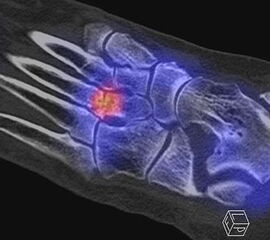

Abbildung 1.1. zeigt eine isolierte aktivierte fortgeschrittene Arthrose des 3. Lisfranc-Gelenkes am linken Fuß. Klinisch bestanden belastungsabhängige Schmerzen plantar im Mittel-/Vorfuß.

Zum Lesen der Bildbeschreibung und zur Vollansicht bitte die Bilder anklicken. Bilder: H. C. Rischke